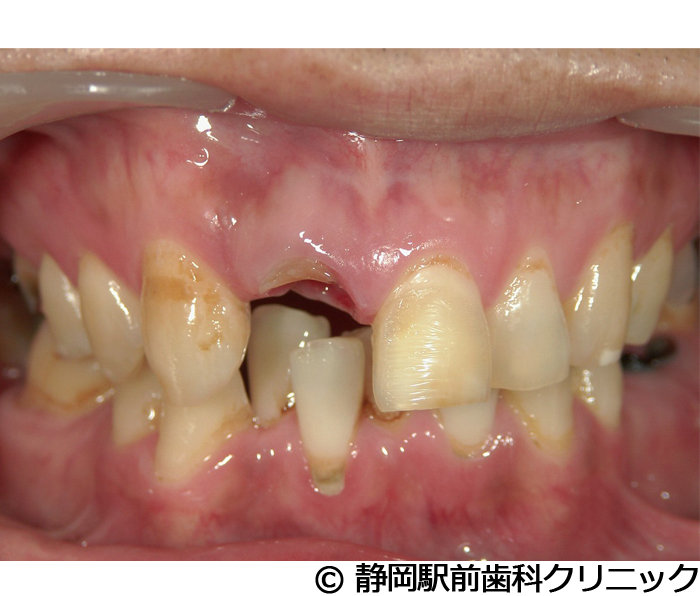

【症例5】全顎的インプラントとセラミックによる審美補綴

- 治療前

- 治療後

- 治療名

- 全顎的インプラントとセラミックによる審美補綴

- 費用

- 1,800,000円(税込)

- 期間

- 1年6ヵ月

治療内容

患者様の症状

全体的に歯がないため、噛めない。インプラント治療希望。

治療方法

全体的に残根は抜歯を行い、術前にCTを撮影し緻密に治療計画を立てた。インプラント埋入はブロックごとに行い、噛み合わせの調整を重ねた後、人工歯を被せて咬合と審美の回復を行いました。

治療結果

しっかり奥歯で食べ物を噛み切ることができるようになり、何でも食べることができるようになったと喜んでいただくことができました。口元を気にせずに笑うこともできるようになり、見た目もキレイになったとご満足いただけました。

※治療結果は個人差があります。

治療を行う上での注意点(リスク・副作用)

術後は、出血、腫れ、痛みなどが出る可能性があります。